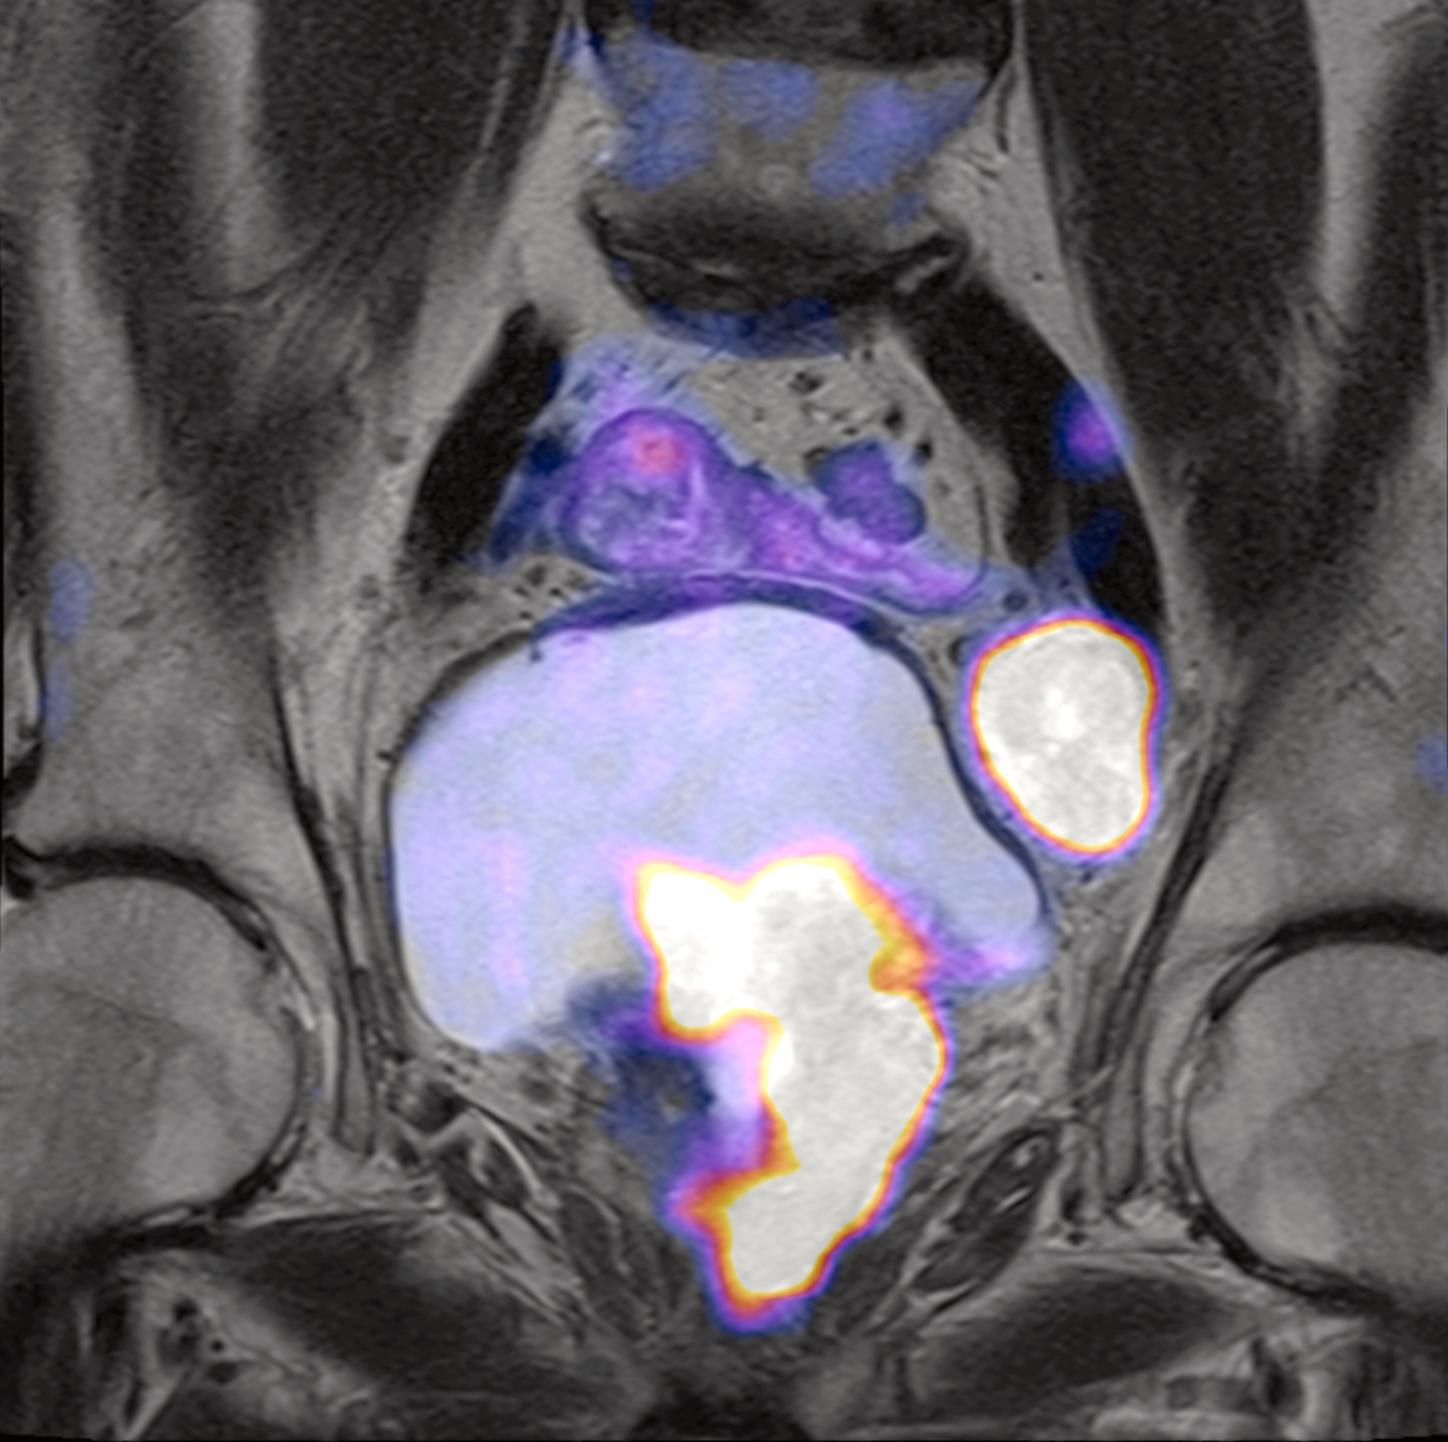

PET/RM en cáncer de próstata

Revisaremos las ventajas de la PET/RM con PSMA para el diagnóstico, estadiaje, evaluación de respuesta terapéutica y seguimiento del cáncer de próstata.